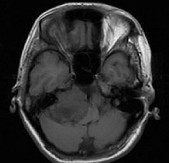

[单选题]女,45岁,右耳听力下降半年余,CT检查如图,最可能诊断为()A.继发性胆脂瘤B.脑膜瘤C.三叉神经瘤D.原发性胆脂瘤E.听神经瘤

[单选题]女,45岁,右耳听力下降半年余,CT检查如图,最可能的诊断是()A.继发性胆脂瘤B.脑膜瘤C.三叉神经瘤D.原发性胆脂瘤E.听神经瘤

[单选题]女,45岁,右耳听力下降半年余,CT检查如图,最可能的诊断是A.继发性胆脂瘤B.脑膜瘤C.三叉神经瘤D.原发性胆脂瘤E.听神经瘤

[单选题]女,45岁,右耳听力下降半年余,CT检查如图,最可能的诊断是( )。A.继发性胆脂瘤B.脑膜瘤C.三叉神经瘤D.原发性胆脂瘤E.听神经瘤